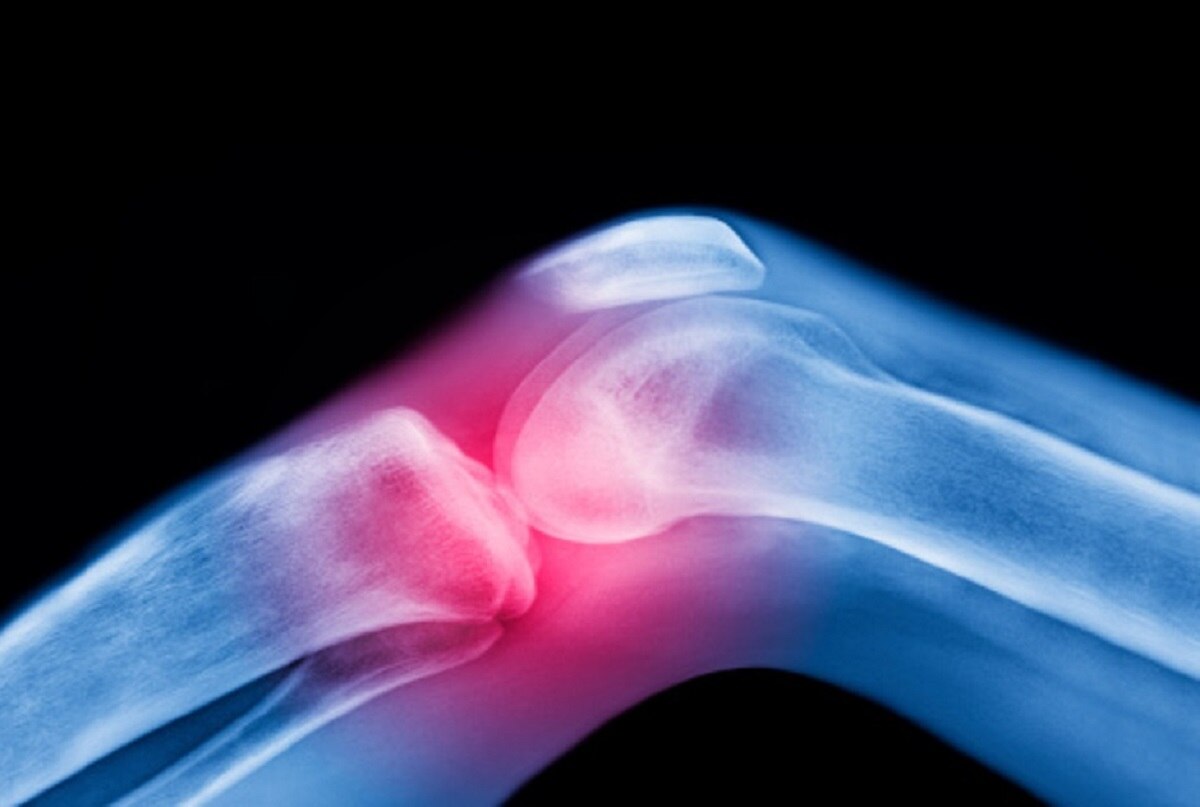

क्या हैं लक्षण- AVN के मरीजों में कई तरह के सामान्य लक्षण देखे जा सकते हैं. उन्हें कूल्हे और कमर में दर्द की समस्या हो सकती है. खड़े होने या चलने में भी परेशानी हो सकती है. जोड़ों में बहुत दर्द रहने लगता है. इसलिए शरीर में इस तरह के लक्षणों को बारीकी से देखें और समय पर जांच जरूर कराएं.

Photo Credit: Getty Images